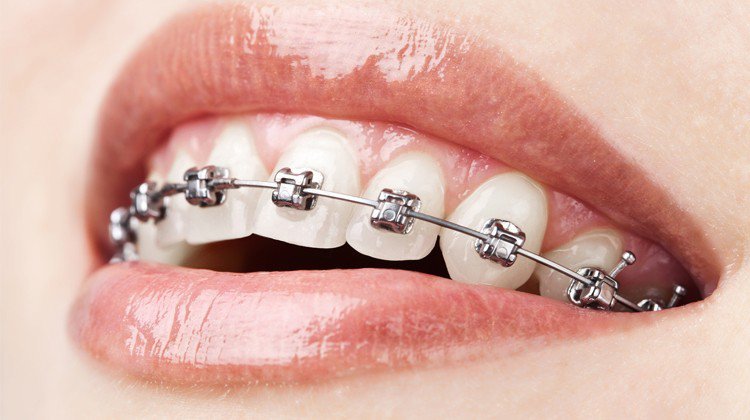

Niềng răng mắc cài là phương pháp sử dụng mắc cài kết hợp với dây cung và các khí cụ chỉnh nha để tạo lực kéo, dịch chuyển răng về đúng vị trí mong muốn, điều chỉnh các sai lệch xương hàm, khắc phục khuyết điểm hô, móm, răng thưa, chen chúc. Đây là phương pháp mang lại nụ cười mới không chỉ đẹp mà còn khoẻ mạnh. Khách hàng có thể lựa chọn mắc cài bằng sứ thay vì kim loại để tăng cường tính thẩm mỹ nụ cười và sự tự tin trong quá trình điều trị niềng răng.

Tại VSiTa Dental, chúng tôi cung cấp giải pháp mắc cài kim loại, mắc cài khoá kim loại, mắc cài mặt lưỡi và mắc cài sứ. Mắc cài kim loại truyền thống có nhược điểm về thẩm mỹ, tuy nhiên lại mang lại kết quả điều trị khá ổn định. Mắc cài có khoá tự động (mắc cài tự buộc) có các chốt thay cho dây thun ở trường hợp mắc cài thông thường, do đó không cần thay thun, giảm thời gian tái khám. Tuy nhiên những chốt kim loại này khá to và vướng víu.

Mắc cài sứ là giải pháp đắt tiền nhất, cải thiện phần nào độ thẩm mỹ của các khách hàng niềng răng đang trong quá trình điều trị. Vật liệu sứ với bề mặt trơn láng nên khách hàng cũng sẽ cảm thấy dễ chịu, bớt vướng víu hơn, tuy nhiên mắc cài sứ sẽ dễ gãy vỡ nếu không được sử dụng cẩn thận.